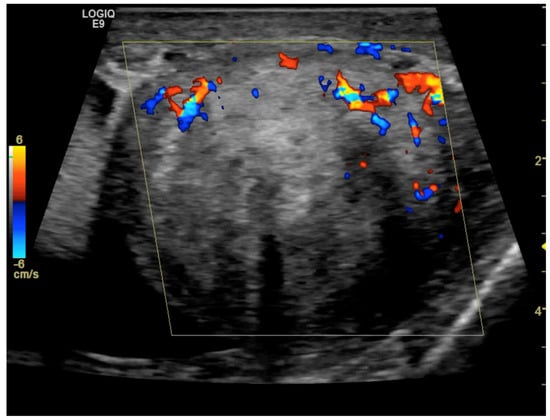

CD was employed to determine the vascularization of the mass. To maximize sensitivity to slow flow velocities, CD was performed using the highest signal gain setting possible (without the appearance of background noise) and low pulse repetition frequencies, allowing for the demonstration of peripheral lesional vascularity (Figure 3 and Video S2). A grade 4 varicocele was also diagnosed via Doppler sonography: dilatation of the veins of the pampiniform plexus around the testis to over 2.5–3 mm and backward flow toward the testes during Valsalva’s maneuver were observed (Figure 4).

Figure 4. Color Doppler image obtained using 15 MHz high-frequency transducer shows serpentine, dilated veins up to 2.5–3 mm in diameter at the inferior pole of the testis, which is consistent with a varicocele. In the spectral Doppler image, backward flow toward the testes during Valsalva’s maneuver was demonstrated (not shown).